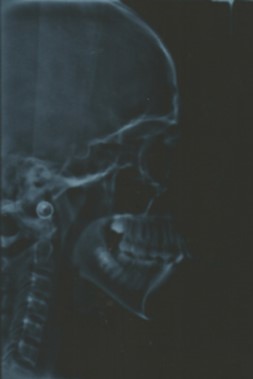

Cephalometric analysis revealed a skeletal Class II pattern, with an orthognathic maxilla and retrognathic mandible with high mandibular plane angle and severely proclined maxillary and mandibular incisors with increased lower anterior facial height. (Figure 3).

Post treatment lateral cephalometric radiograph was taken to assess the treatment changes. (Figure 9). The changes in maxilla in the anteroposterior direction was insignificant, however an increase in the length of the mandible measured from Condylion (Co) to Gnathion (Gn) and an increase in anterior facial height was observed. Maxillary incisors were retracted dramatically by 8mm and the mandibular incisors were proclined by 3mm to camouflage the skeletal class II malocclusion.(Table 1). Effective expansion of the maxillary constriction as an end-of treatment goal was achieved. (Figure 10a,Figure 10b).

Figure 9.Post-treatment lateral cephalometric radiograph